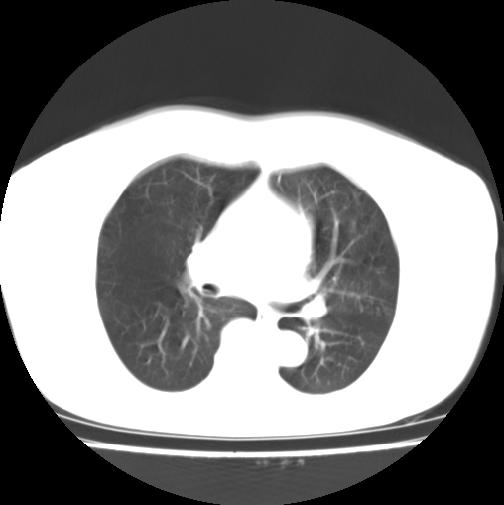

女性病人,56岁,反复咳喘30余年,伴大量脓痰,偶有痰中带血。

此病例在科室里有较大的争议,我认为是先天性肺囊肿(理由是:两者起病年龄都较轻,都有咯血及脓痰的症状,而先天性肺囊肿壁薄;而支扩的囊腔旁一般都能看到伴行的血管影,形成“印戒”征)。以上为个人的意见,请高手们指点一下。

本例应为支气管扩张并感染,与囊肿区别在于其大小,分布,壁改变,与肺动脉关系,形态等来鉴别,要点大家都说得差不多了,囊肿要大些,分散些,靠外围一些,而支扩靠内一些,聚拢些,小一些且易聚拢呈葡萄状,不能单从囊壁厚度来评价,特别是有粘液栓类的改变更加支持支扩,有时支扩亦与囊肿混在一起并存.个人意见仅供参考.